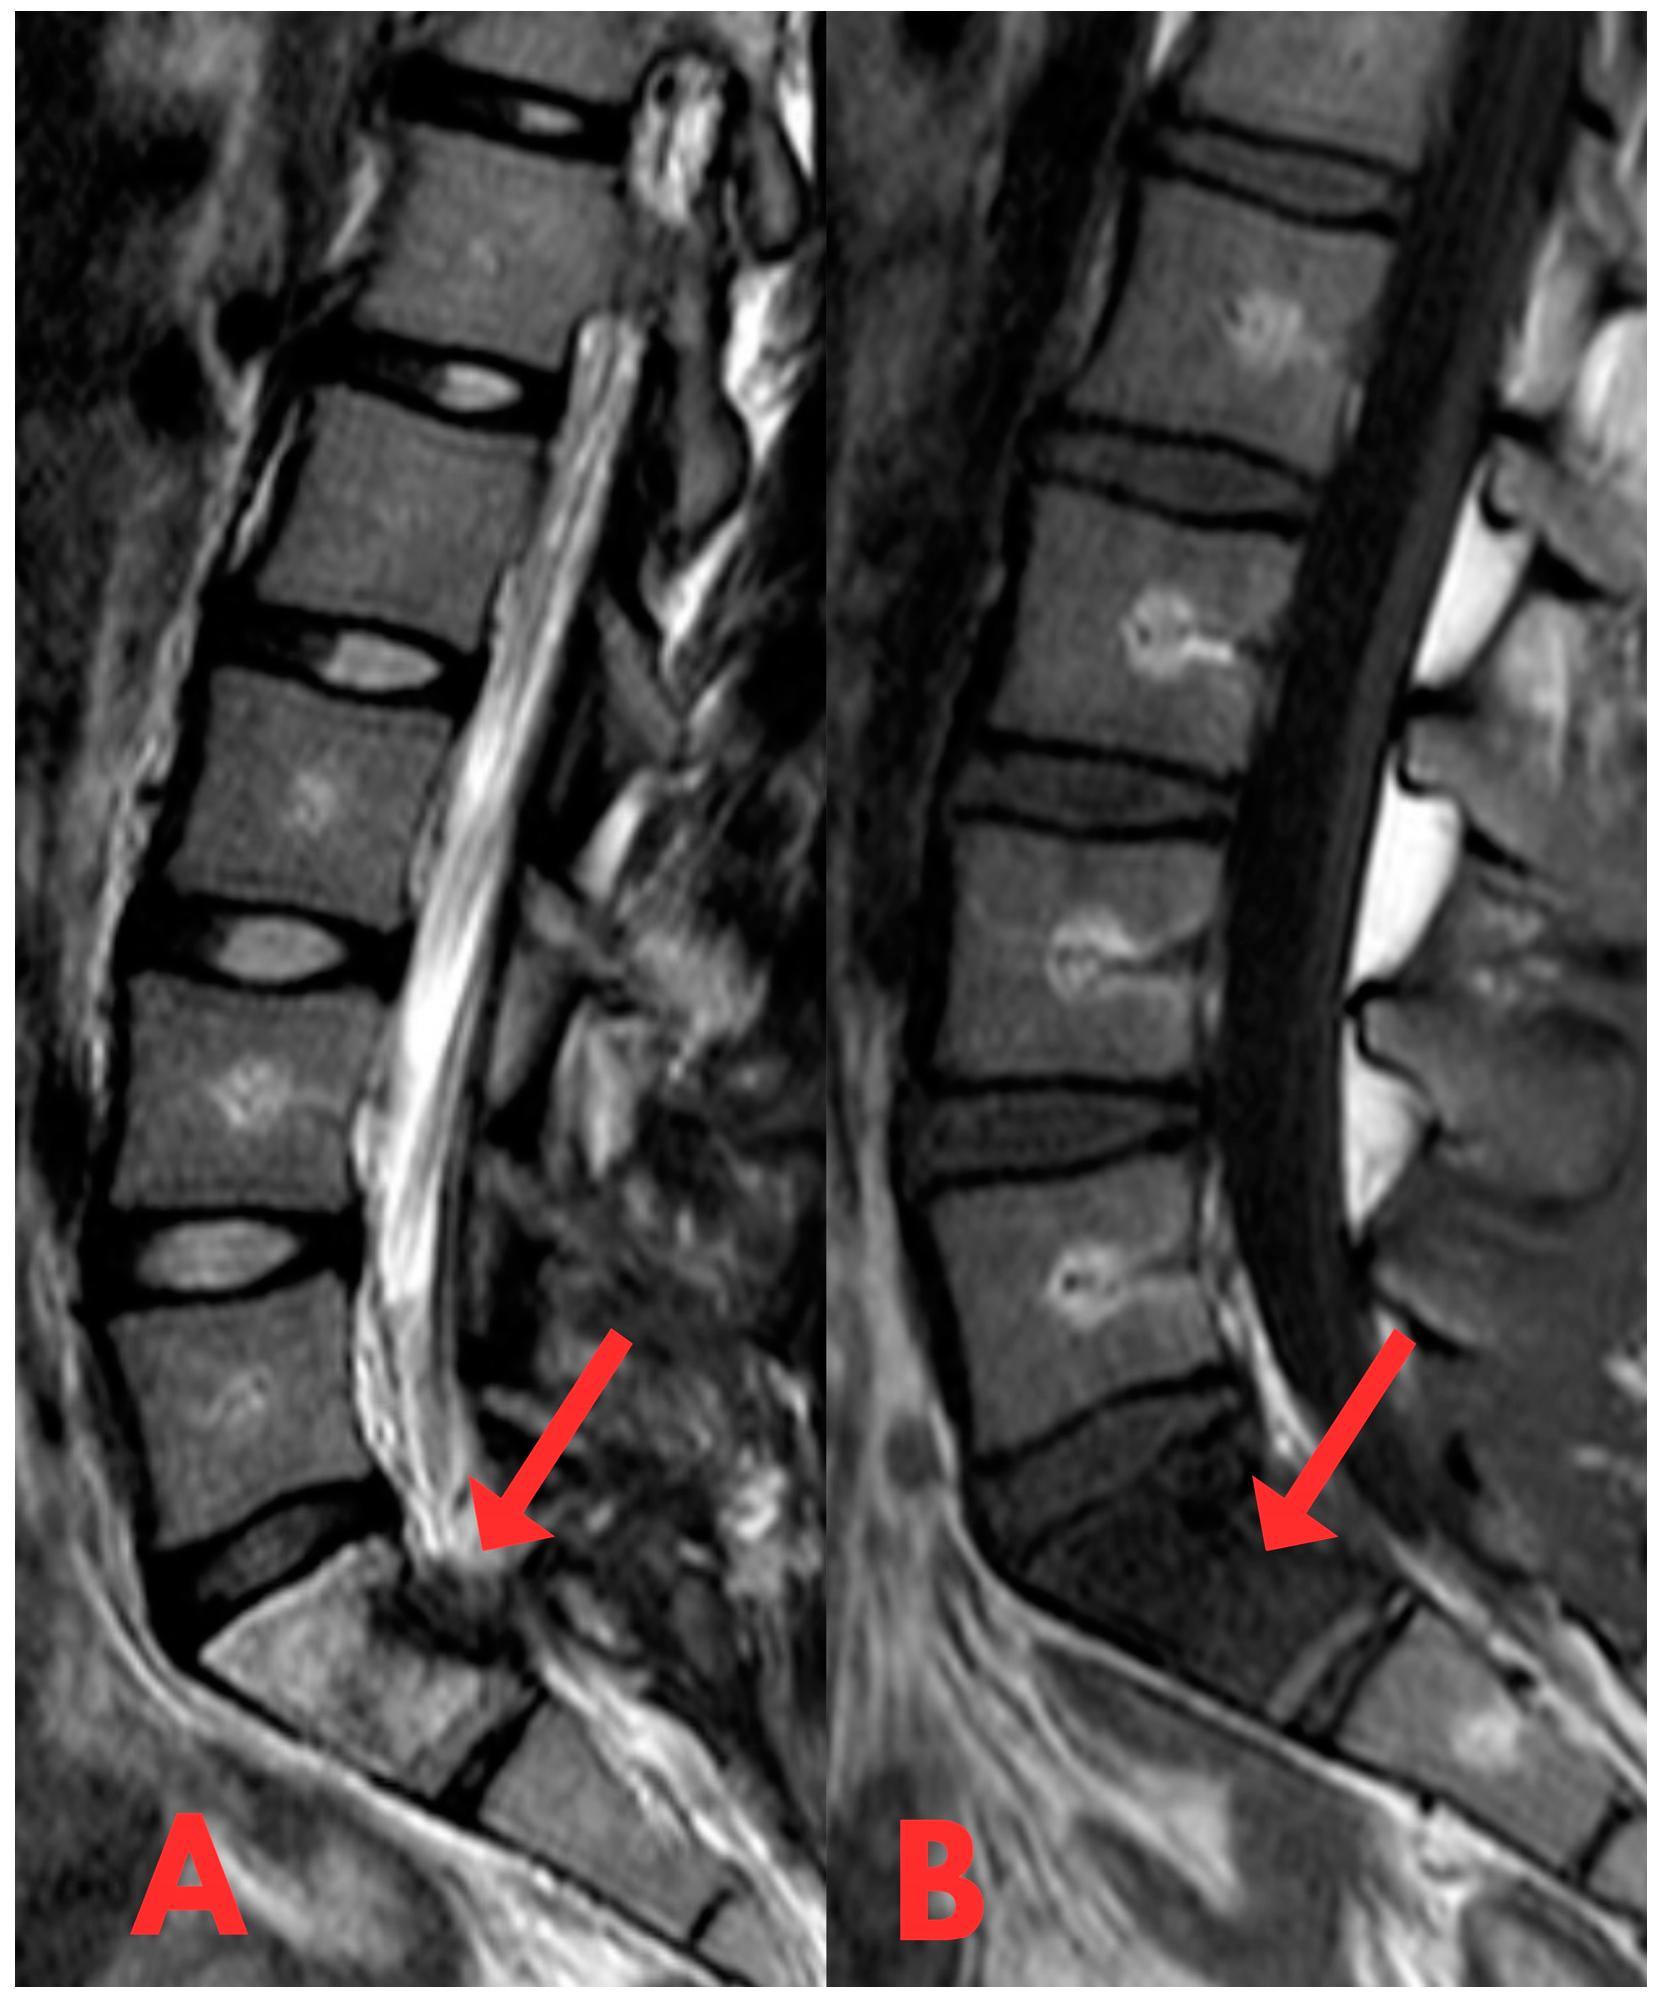

The patient was neurologically intact but reported localised pain exacerbated by bending backward. No external abnormalities were observed and there was no relevant medical history of secondary illnesses or oncological diseases. A biopsy was performed with a 3.5 mm vertebroplasty needle. The obtained material was sent for histological examination. The histological response did not indicate significant findings. The diagnoses, fibrous dysplasia on MRI, and histologically small fragments of bone trabeculae did not provide a basis for a more surgically aggressive or conservative specific treatment method. Therefore, it was decided to perform a repeated open biopsy, to clarify the diagnosis and to examine the structure of the lesion under an operating microscope. A repeat MRI examination of the lumbar spine was performed, revealing a persistent high-signal lesion in the S1 vertebral body (Figure 4 and Figure 5), suggestive of fibrous dysplasia. Compared to the previous MRI, there were no changes in the dynamics of the radiological image.

Figure 4.

(A,B) Second T1- and T2-weighted sagittal MRI of the lumbar spine (T2W_TSE, T1W_TSE sag) showing no significant change in the S1 lesion. In dynamics, there is a small signal change in the posterior 1/3 of the S1 vertebra body after a biopsy with a small defect.